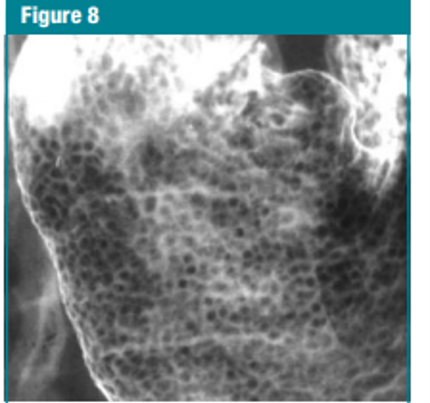

gastric erosions in antrum

Gastric erosions or aphthous ulcers are superficial ulcerations that do not penetrate the muscularis mucosa. They usually appear as small, shallow collections of barium 1–2 mm in diameter surrounded by a radiolucent rim of oedema. These are called ‘complete’ or ‘varioliform’ erosions (Fig. 27-6A).